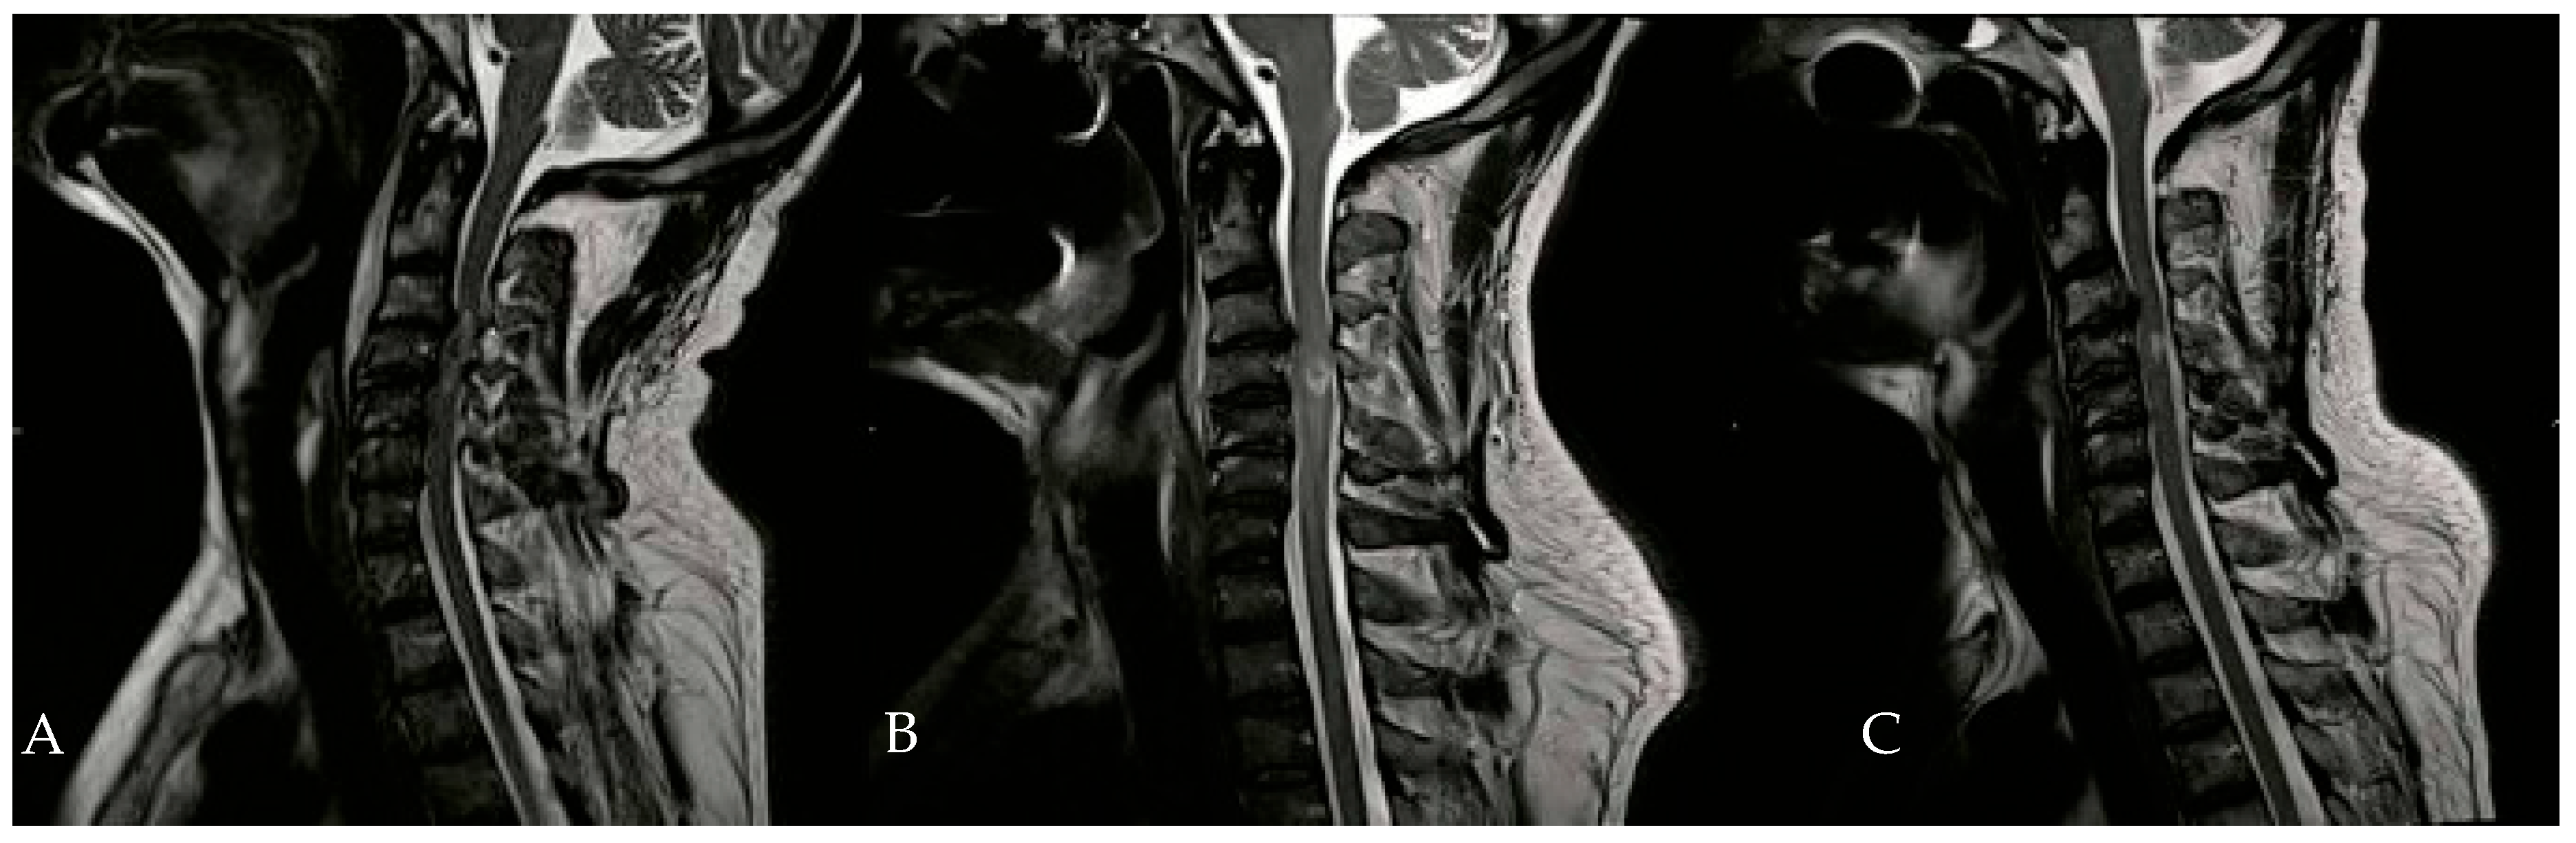

In addition to HBOT, the patient received heparin, dexamethasone, omeprazole, and a combination of amoxicillin and clavulanic acid. An Ear, Nose, and Throat (ENT) evaluation revealed a slight adductor deficit of the vocal cords and a minor glottic incompetence due to a superior laryngeal nerve deficit. On the second day of HBOT, hypertonia of the flexor muscles in both hands was noted, prompting the initiation of twice-daily physiotherapy sessions. By the tenth day of HBOT, significant clinical improvements were observed, including the recovery of anal sphincter control, full recovery of neck flexor and extensor muscles, and improved phonation. Subsequent neuroradiological examinations during hospitalization showed a gradual reduction in spinal cord edema (Figure 3).

Figure 3.

Evolution of hematomyelia in cervical MRI, performed 5 days (B) and 30 days (C) after the initial MRI (A).

The patient completed 19 sessions of HBOT, with the neurological level of injury remaining at C4, but improved from AIS B to AIS D. After one month of HBOT, the patient was discharged to a neuro-rehabilitation center for an additional six months of treatment. At the final follow-up, the patient’s neurological examination revealed diffuse spastic hypertonia and a neurogenic bladder. Upper-limb motion showed paralysis in the right-hand flexors and the left elbow and hand extensors, with moderate motor recovery (3/5) in the lower limbs. The patient achieved sufficient recovery to sit and move independently using an electric wheelchair. With regard to autonomic function, no clinically documented episodes of autonomic dysreflexia were observed during the monitored hospital course. Similarly, no clinically significant episodes of orthostatic hypotension requiring specific therapeutic intervention were reported. Bladder and bowel function progressively improved during rehabilitation, in line with the overall neurological recovery.